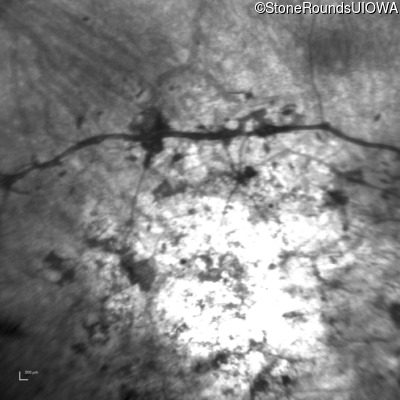

Age at visit: 33 years